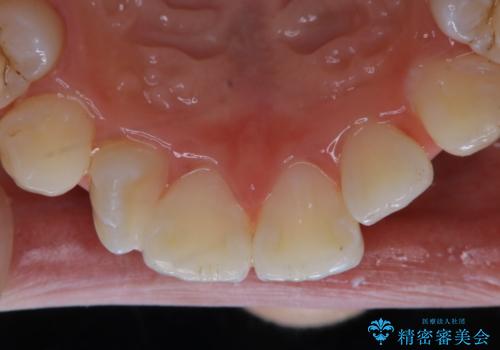

- インビザラインでの矯正治療中の方です。全体的に黄ばみ・黒ずみが気になるとのことでした。

PMTC60分コースを行いました。

PMTC(保険外治療)は、毎日の歯磨きで落としきれない汚れや、コーヒ、紅茶・タバコのヤニなどの着色も除去します。目には見えない歯と歯の間・歯肉の境目・インビザライン中はアタッチメント周囲などに残っているプラーク(歯垢)もしっかり取り除きます。PMTCでは専門的な機械や材料を使用して、徹底的に汚れを除去するため、虫歯・歯周病・口臭予防などにつながります。

またPMTCを行うことで、ご自身本来の歯の色になり自然な明るさになります。